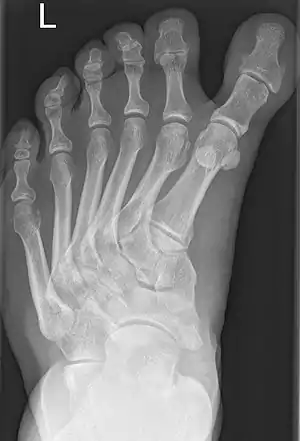

Polymetatarsia is a rare congenital malformation which is characterized by the presence of 6 or more metatarsal bones in the same foot. It is most commonly seen alongside polydactyly,[1] and it often appears between the fourth and fifth metatarsals or beside the fifth metatarsal.

| Polydactyly-associated polymetatarsia. | |